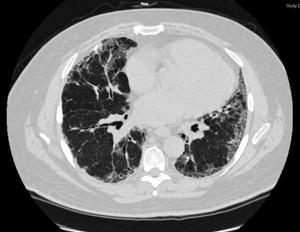

A high resolution CT scan of the chest showing a bilateral peripheal reticular pattern and subpleural honeycombing of the lungs